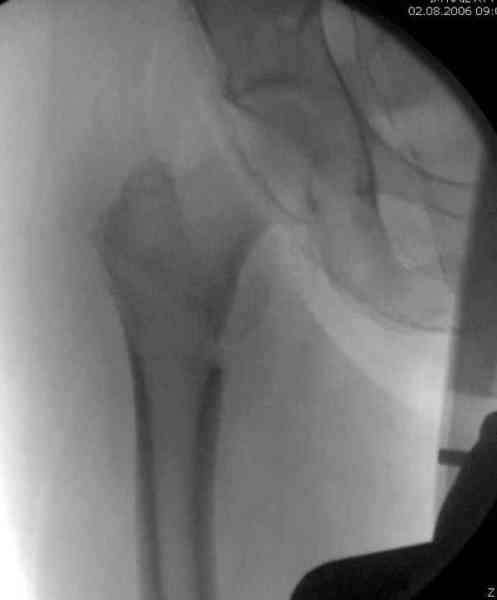

В течении последних двух лет на рынке появились множество других трохантерных штифтов, включая TTFN helical screw Synthes, вот недавно Smith Nephew Richards заимел новый имплант, азработанный Roy Sanders.

Мы получили испытательный вариант инструментария для пробы, хотя компания объявила, но ещё не для широкой публики, обещают к сентябрю. За полтора месяца, включая сегодняшнюю, вот уже восьмая операция по счету. Удобный инструментарий, ничего лишнего, научились делать быстро, посмотрим что будет, пока нравится.

Все больные пожилого возраста, первые уже успели появиться на амбулаторном приеме, пока без осложнений.

Здесь сканнированные снимки импланта и операционные снимки больной.

На этом снимке процесс компрессии нижним болтом.

Итог